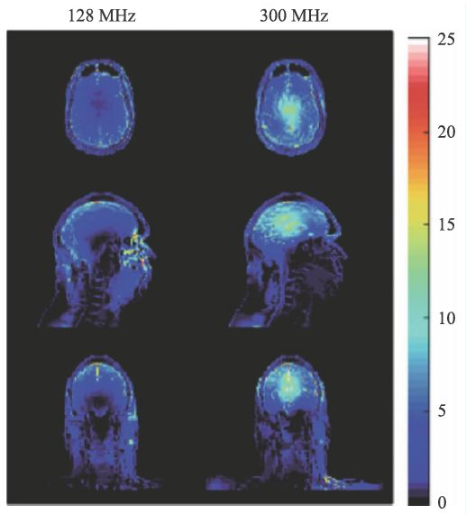

超高場MRI的射頻場設計也是一個較為困難的問題。由于射頻頻率超過了300 MHz,介電常數引起的問題非常突出。圖13 是一個在7 T 下的成像結果,可以看到在圖像內部的信號非常不均勻,由于射頻波長的極度縮短,組織的介電常數對射頻場的分布有極大的影響,這也是目前超高場MRI 需要解決的重要問題之一。目前的9.4 T以上的MRI設備還難以獲得人體體部掃描的良好圖像,其主要應用還是做頭部的掃描。

圖13 超高場下的射頻場不均勻性

SAR值升高是射頻場另一個問題,隨著射頻頻率的提高,組織對射頻能量的吸收急劇上升,可導致組織局部的溫度升高。SAR值的計算可由式9表示。

σ為組織電導率,ρ為組織密度。對于SAR值各國和國際組織均有嚴格的限制,因為過量的射頻能量的吸收可能會對受試者造成危害。

圖14 是一個SAR值對大腦溫度升高的一個仿真結果[14],對于平均SAR=3 W/kg的頭部掃描,7 T(右側)下的溫度升高顯著高于3 T(左側)。因此在超高MRI中均需要配置一個可靠的SAR值監控裝置。

圖14 局部SAR值的仿真結果